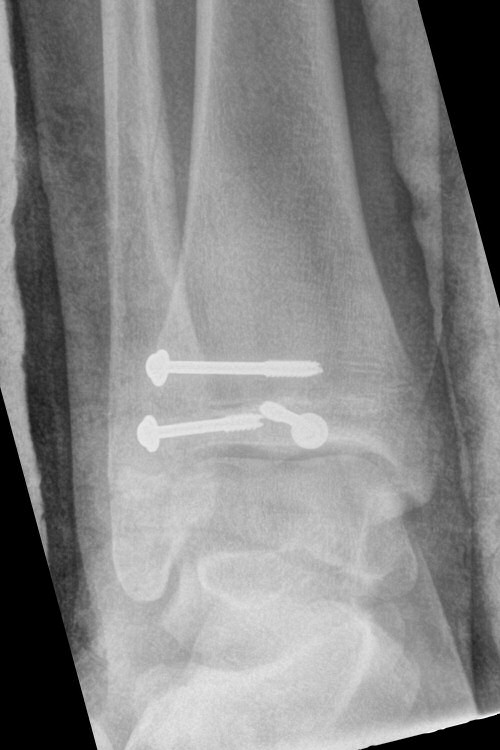

Exempel på triplansfraktur hos nästan färdigvuxet barn

På akutmottagning

Distal tibiafyseolys SH 4 triplansfraktur (barn)

Triplanfraktur = triplansfraktur = treplansfraktur: fraktur i distala tibia som engagerar både metafys, fys och epifys. Kan vara 2, 3 eller 4 fragment. I 50 % av fallen är även fibula frakturerad [3].